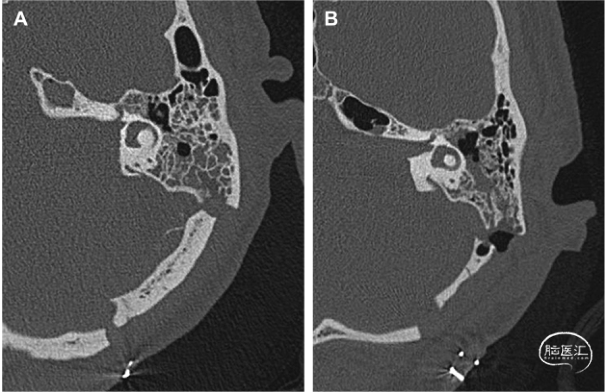

图3. CT轴位成像显露内听道底暴露的程度。A. 完全显露:磨除内听道后壁和顶壁后开颅至面神经管开口的手术路径;B. 未显露:内听道后上壁在内听道底的残余外侧部分。

图4. 依据CT轴位成像确定开颅骨窗后内侧缘示意图。A. 辨认乙状窦;确认内听道底—迷路线(FLL);FLL后内侧11.3mm处;确定开颅骨窗的后内侧缘;从乙状窦到开颅骨窗内侧缘的距离。B. 开颅骨窗的三维透视。